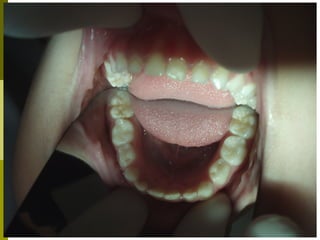

Προληπτικά μέτρα - Καλύψεις οπών και

σχισμών (ΚΟΣ)

 (Προληπτικές εμφράξεις, προστατευτικά, αποφράξεις οπών και

σχισμών, sealants)

   Οι μασητικές επιφάνειες των οπισθίων δοντιών

ευνοούν την κατακράτηση τροφών και μικροβίων και

συχνά τερηδονίζονται αμέσως μετά την ανατολή τους.

 Οι καλύψεις οπών και σχισμών είναι

εύκολες στην τεχνική αλλά και ευαίσθητες.

 Καλή απομόνωση δοντιού, χημική

επεξεργασία (αδροποίηση) και συγκόλληση

ενός ρητινώδους υλικού.